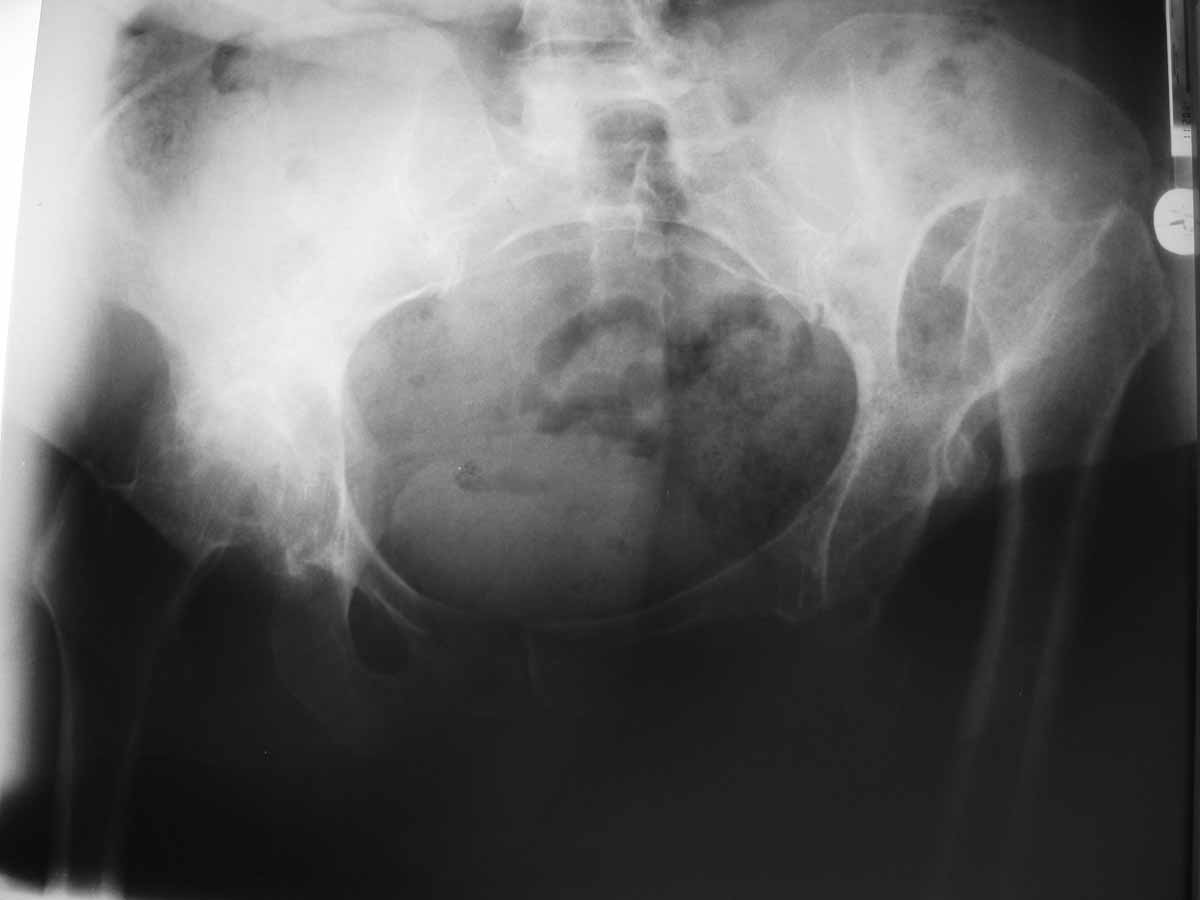

Доброго времени суток уважаемые коллеги, к нам поступила больная 58 лет с правосторонним

неоартрозом, левосторонним анкилозом тазобедренного сустава, деформирующий гонартроз

II-III степени с обеих сторон, укорочение правой нижней конечности на 5.7 см. Больная

жалуется на боли в коленном и тазобедренном суставах слева. Больная сохранна, хотелось бы

услышать мнения по тактике лечения больной.